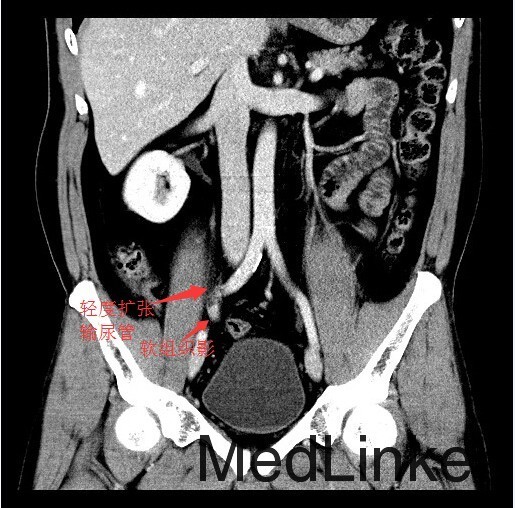

查体:肛门括约肌稍松弛,前列腺明显增大,大小约:4×3cm,表面光滑,质韧,边缘清楚,中央沟变浅,未触及明显结节,指套未见染血。 辅查:CT示:右侧输尿管下段软组织肿块影,考虑输尿管癌可能,相应输尿管中上段、右肾肾盂扩张积水

讨论:输尿管恶性肿瘤多来源于输尿管上皮组织,以移行细胞癌最常见,移行细胞癌多呈乳头状生长,突入腔内,约1/3为多发性肿瘤。影像表现为输尿管、肾盂和肾盏不同程度扩张积水,并于输尿管梗阻端发现软组织肿块或腔内有充盈缺损,增强扫描轻中度强化,集合临床表现,多可作出诊断,不过应注意输尿管癌的多发性,勿漏诊!